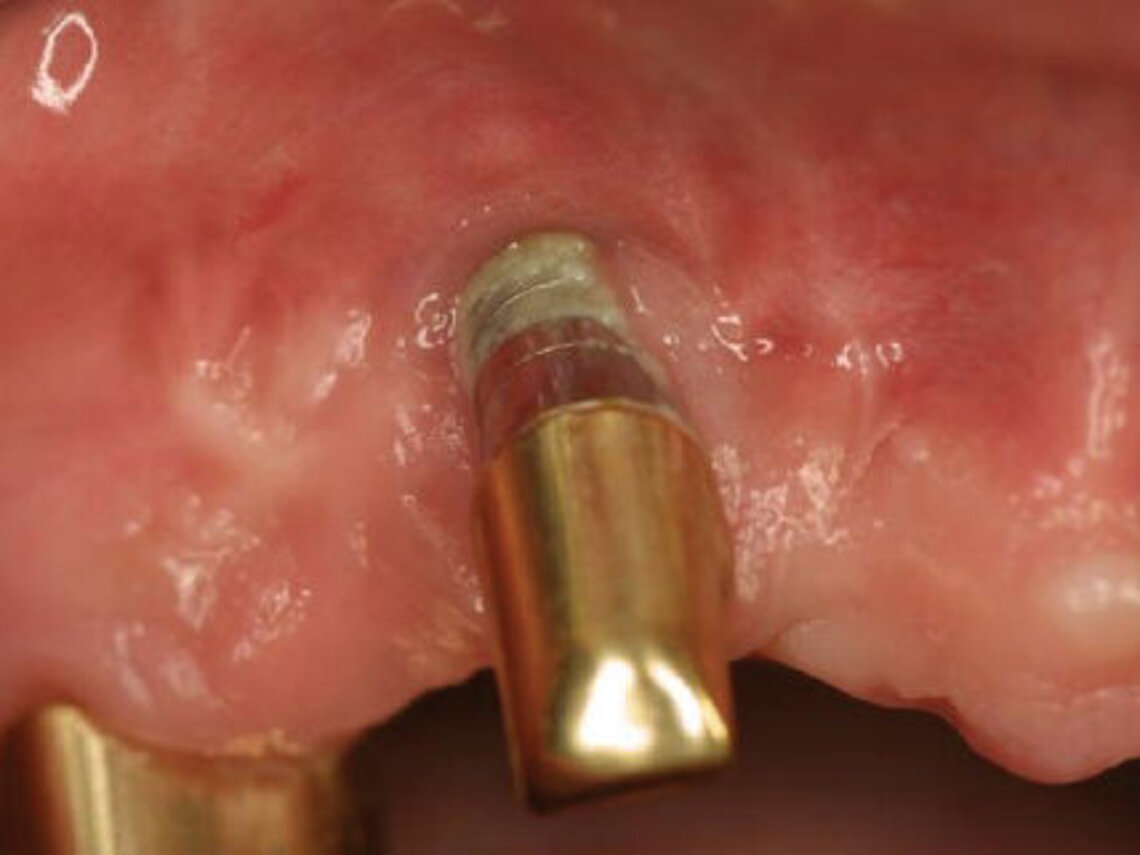

Recently, ceramic implants were introduced as alternative strategy with the aim of preventing the development of peri-implantitis and bone loss (Fig. 6). Compared to titanium implants, studies show that zirconia implants are associated with lower plaque and bleeding scores.15-17 Ceramic implants offer high resistance to corrosion, better peri-implant soft tissue conditions and less inflammation as well as lower oral biofilm adhesion. Apart from the excellent mid-term clinical outcomes, such as a high cumulative survival rate and a low level of average crestal bone loss, zirconia implants contribute to the aesthetics of dental restoration. The white color of zirconia comes close to that of natural teeth.15,18 If the long-term clinical results of ceramic implants are confirmed to be equal to or better than the metal alternative, there is potential for a general switch to ceramics in the future.

Based on current evidence and studies suggesting that zirconia dental implants are associated with less peri-implant inflammatory reactions and less crestal bone loss (Fig. 7), we decided to investigate the behavior, the mechanical stability and the clinical outcomes of ceramic implants at our institution. The first patient implantations look promising. But long-term studies will be required to develop strong evidence and convince the large majority of dental implant surgeons to use zirconia dental implants as routinely as orthopedic surgeons do in hip replacement.